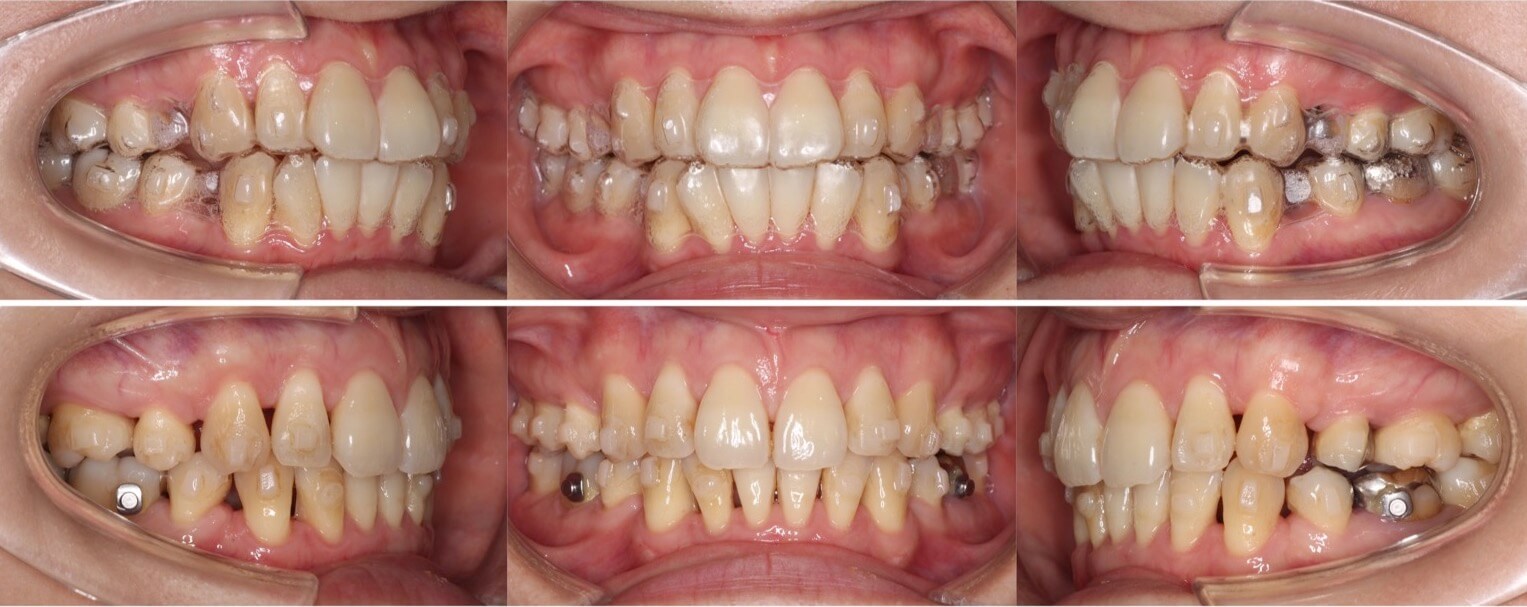

高校生女子・唇側矯正装置・前歯傾斜型

<顔のビフォーアフター>

<症例概要>

主訴:出っ歯とデコボコ

年齢・性別:高校生女子

住まい:千葉県八千代市

症状:叢生・上下顎前突

治療方針:抜歯空隙の閉鎖(最大固定)

治療装置:唇側矯正装置

固定装置:ナンスホールディングアーチ

抜歯:上下左右第一小臼歯抜歯(計4本)

治療期間:1年11か月

リテーナー:上プレートタイプ+下フィックスタイプ

治療費用:968,000(税込)

代表的副作用:痛み・治療後の後戻り・歯根吸収・歯髄壊死・歯肉退縮

▶︎その他の副作用

上下の前歯が前方に傾斜しているため、口が閉じずらい上下顎前突症例です。しっかりと永久歯が生えるまでは、少しでも前歯を後方移動させるためのスペースを獲得するために半年ほどヘッドギア装置を使用しました。その後、小臼歯抜歯を併用し本格矯正治療を行い前歯を約8mmほど後方移動させました。治療後は口元の緊張感もなくなり、すっきりとした横顔になりました。